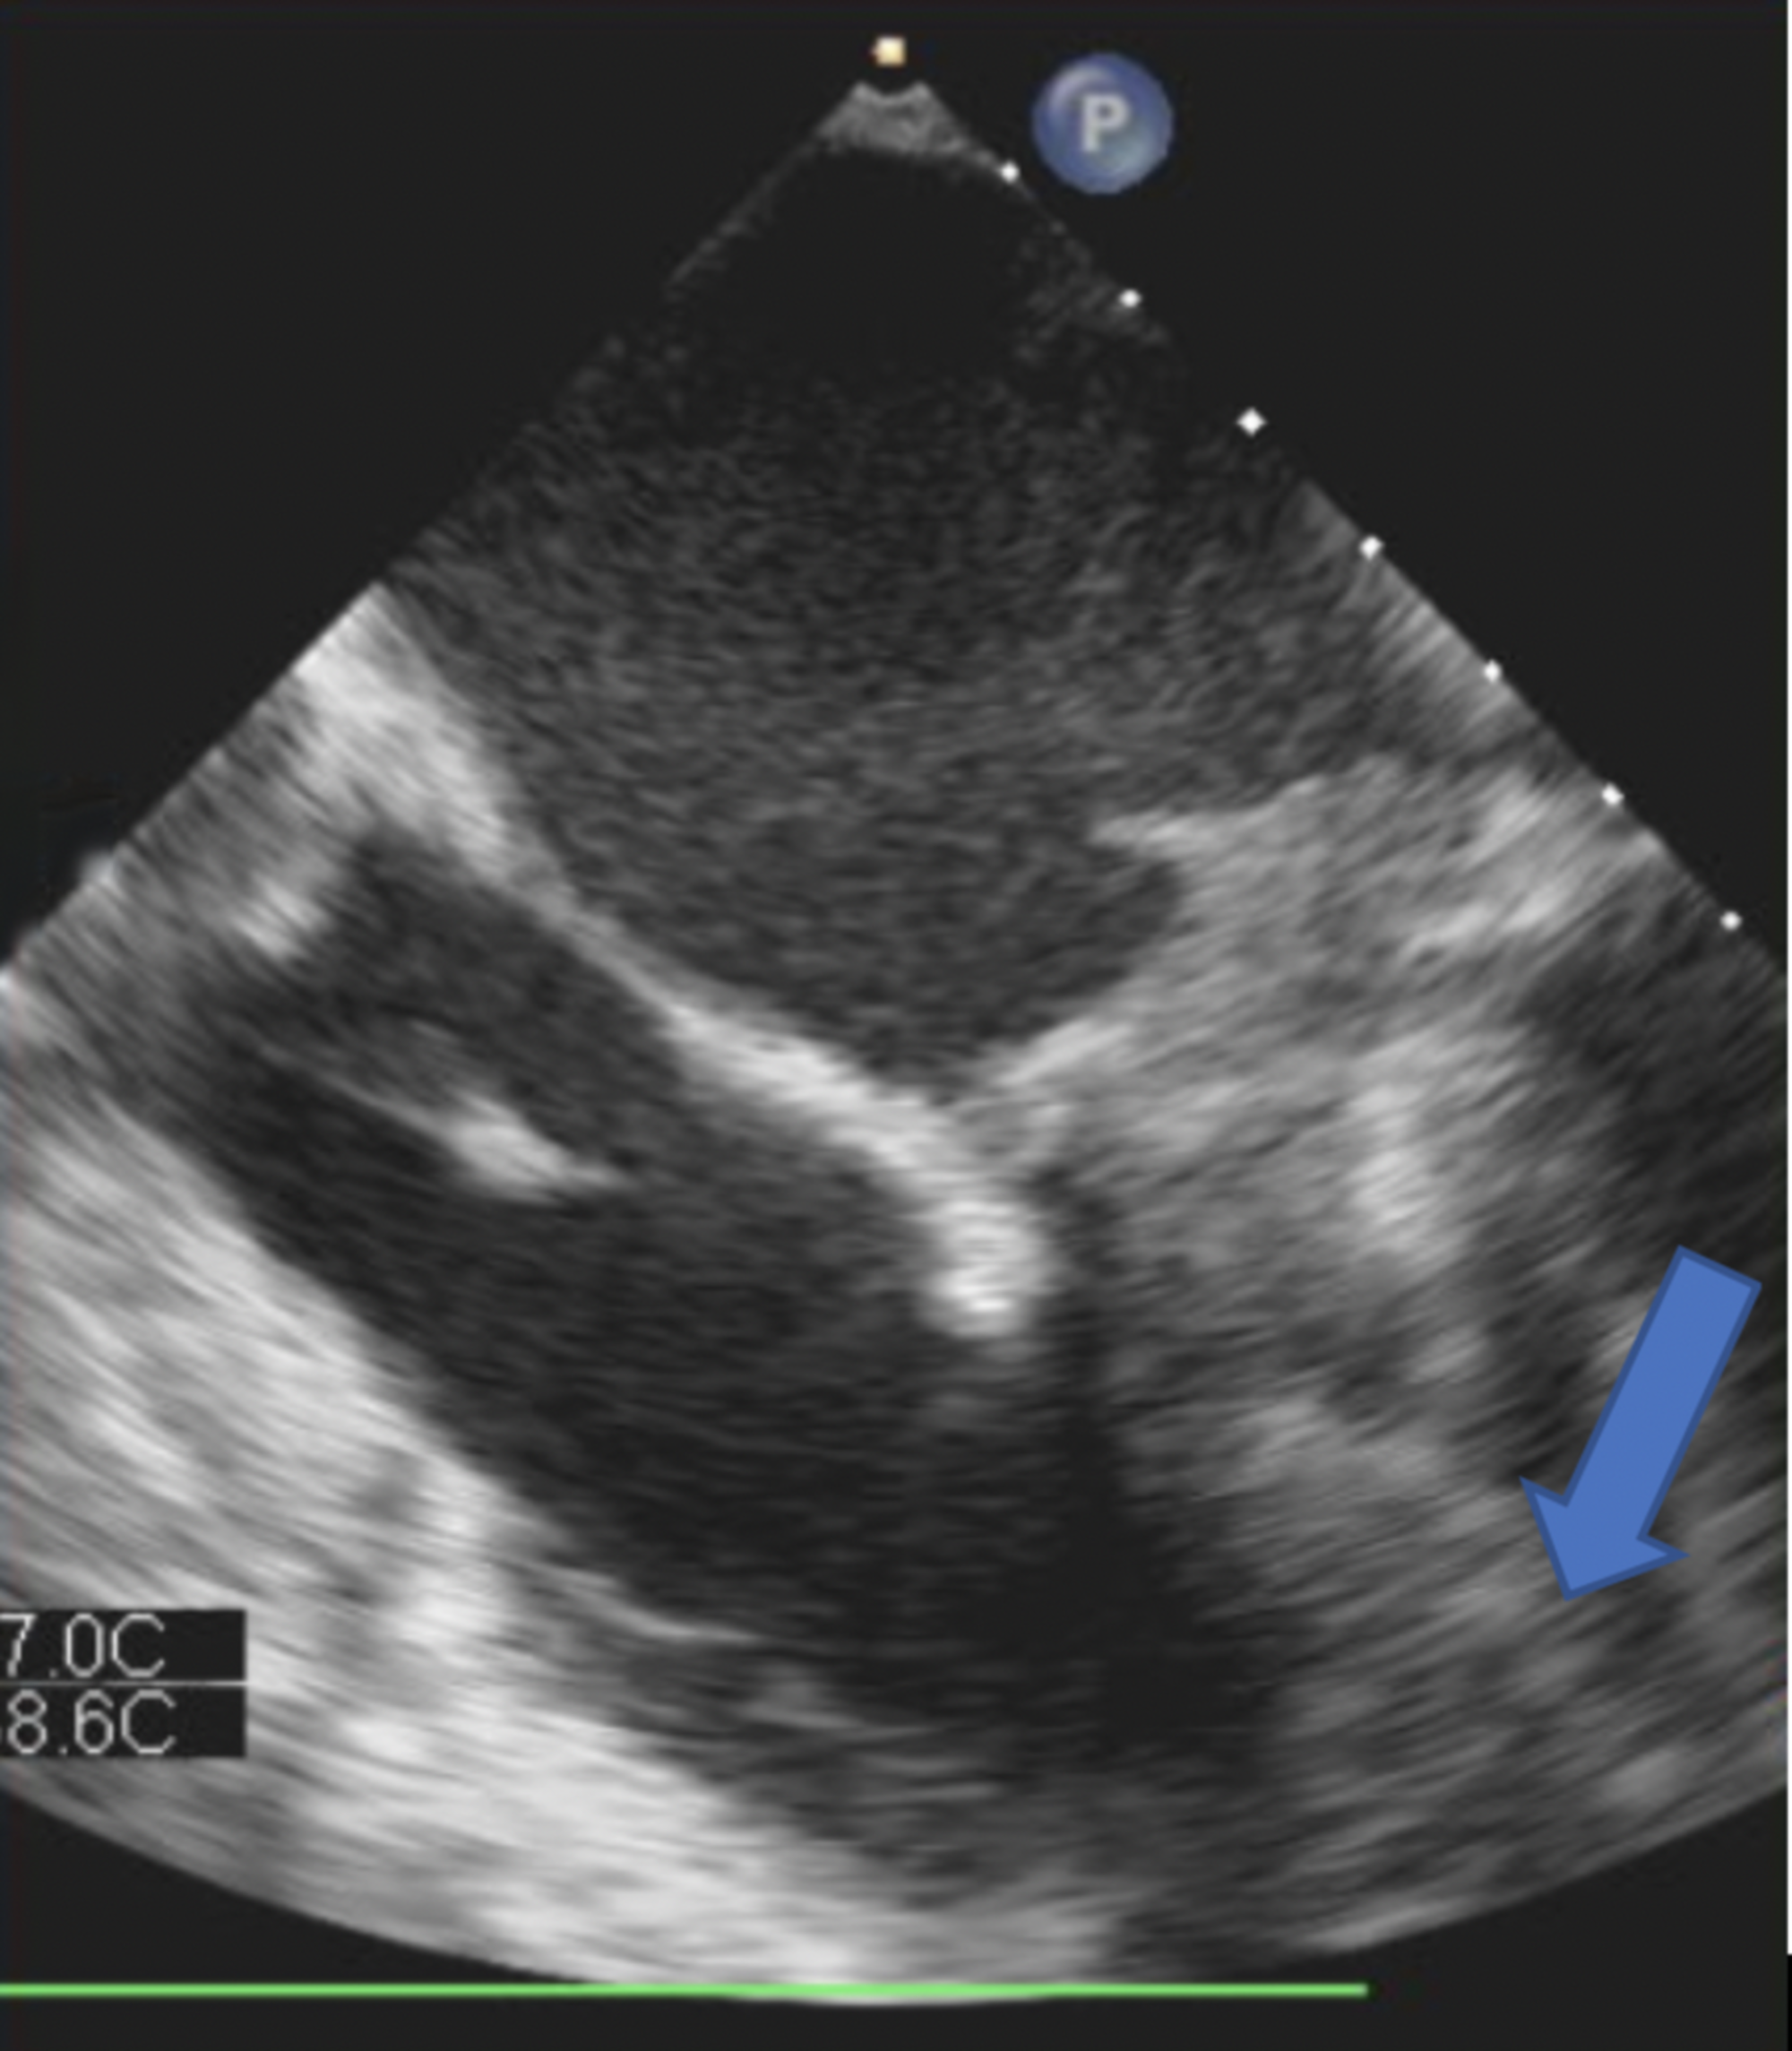

Fulminant thrombosis of mechanical mitral valve prosthesis Heart

Fulminant thrombosis of mechanical mitral valve prosthesis Heart Mechanical Valve Echo The transthoracic approach is complemented with two. This article provides recommendations for evaluating prosthetic valve function with echocardiography and doppler ultrasound. Anticoagulation with vitamin k antagonists (vkas) is recommended to achieve varying international. Doppler interrogation with color and spectral modalities plays a central role in evaluating prosthetic valve function and related. A comprehensive review of echocardiographic assessment of prosthetic mitral. Mechanical Valve Echo.